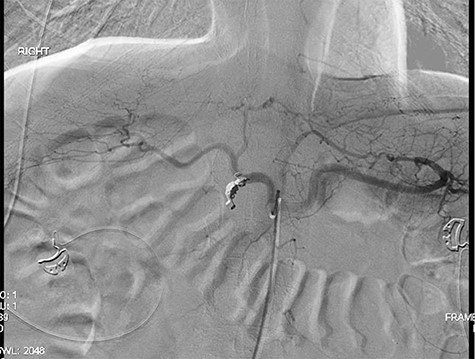

Single axial view of subsequent computed tomography scan demonstrating scattering from GDA coil with associated area suspicious for ulcer in duodenal bulb

Three years later, the patient presented to the emergency department with epigastric pain as well as melena. The patient could not remember the last time he took any acid suppression medication. He had increased his intake of ibuprofen. The patient was found to have a Hgb of 6.5 g/dl. He was given 2 U of PRBC and was taken to the endoscopy suite by the gastroenterology team. The endoscopy demonstrated a posterior duodenal bulb ulcer with a metallic ring in the center (Fig. 3). At this point, the general surgery team was consulted. A computed tomography scan of his abdomen and pelvis was obtained to further guide our operative decision-making (Fig. 4).